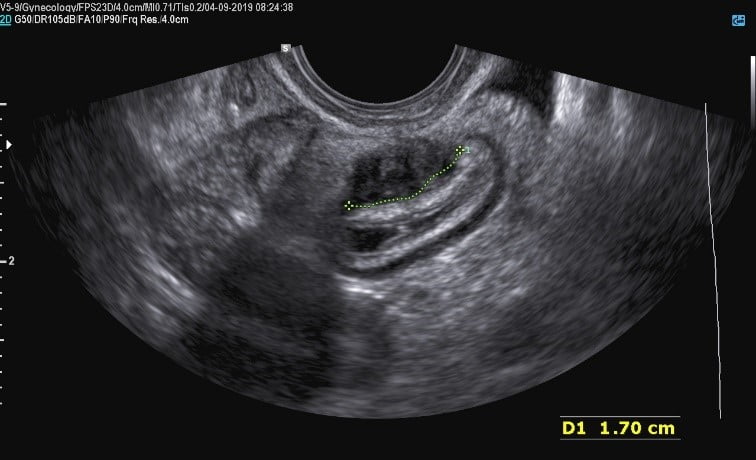

sintomas de endometriose

Imagem de ultrassom transvaginal com preparo intestinal de uma lesão de endometriose localizada no intestino grosso (reto), medindo 1,7 cm no diâmetro transverso.